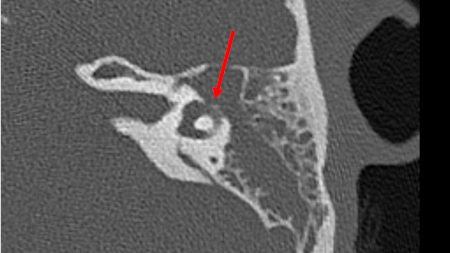

- cholesteatoma

- CT or MRI brain